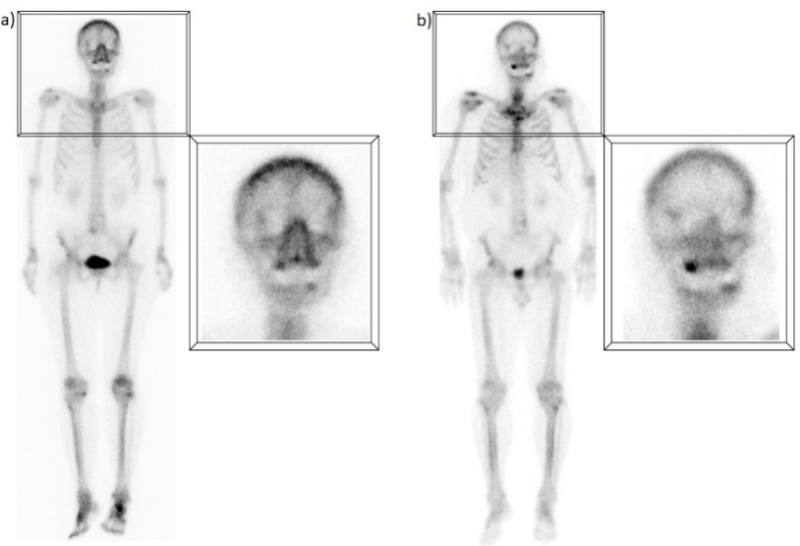

C) Captación del borde orbitario supero-lateral

Se pueden encontrar varios "puntos calientes" en el borde orbitario, aunque los ubicados en el margen supero-lateral son los más frecuentes (46,2%) (4). Aunque generalmente se interpreta como una lesión benigna, por ejemplo quiste dermoide, osteoma, cambio postraumático o incluso captación en la glándula lagrimal, en algunos estudios se ha encontrado que representa, en la mayoría de los casos, una captación benigna en la sutura fronto-cigomática. Con frecuencia, las líneas de sutura exhiben una mayor captación que puede ser secundaria a osificación, presencia de cuerpos de inclusión cartilaginosos calcificados o cambios óseos reactivos de granulaciones aracnoideas(5,6) (fig. 3).

D) Captación del área sino-nasal

Es quizás uno de los hallazgos más frecuentes y su interpretación debe ser cuidadosa, dado que puede representar tanto una patología como una variante normal. A menudo, la captación en la región nasal y maxilar representa la remodelación ósea en las paredes de las cavidades paranasales debido a cambios inflamatorios crónicos(7); esto se ha observado no sólo en pacientes con sinusitis crónica, sino también con rinitis alérgica. Sin embargo, algunos estudios han encontrado que un porcentaje significativo de pacientes (hasta un 42%) sin síntomas respiratorios continúan presentando este patrón de captación, aunque de forma menos prominente(8). En muchos de estos pacientes se ha descrito una captación extra ósea, probablemente secundaria a un mayor flujo sanguíneo y permeabilidad capilar de los tejidos regionales, ya que la mucosa nasal es un área muy vascularizada(9) (fig. 4).